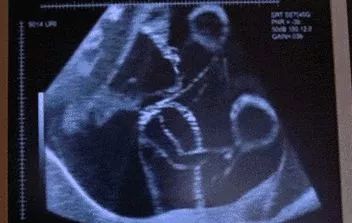

胎动,指的是胎儿在子宫腔里的活动冲击到子宫壁的动作,说白了就是胎宝宝在你肚子里随意翻滚,打打功夫啥的,你明显觉得自己的肚子会动那么几下!胎宝宝在子宫内伸手、踢腿、冲击子宫壁,这就是胎动。

胎动是一件神奇的事情,可以让孕妈感知生命的伟大,了解胎宝的行为动作。当胎宝伸手,踢脚,都会让准妈感受到胎动。怀孕满4个月后,即从第5个月开始孕妈可明显感到胎儿的活动,胎儿在子宫内伸手、踢腿、冲击子宫壁,这就是胎动。胎动的次数多少、快慢强弱等表示胎儿的安危。

胎儿的发育是一个很神奇的过程,从一个小小的受精卵一直发育成熟为三四千克的足月胎儿,这需要怀胎十月漫长的历程。胎儿成形后,一直就在妈妈肚子里活动着,从左到右,从上到下的,一些调皮的胎宝宝会经常在左边或者右边,准妈妈们自然就会发现胎动在左边或者右边了。